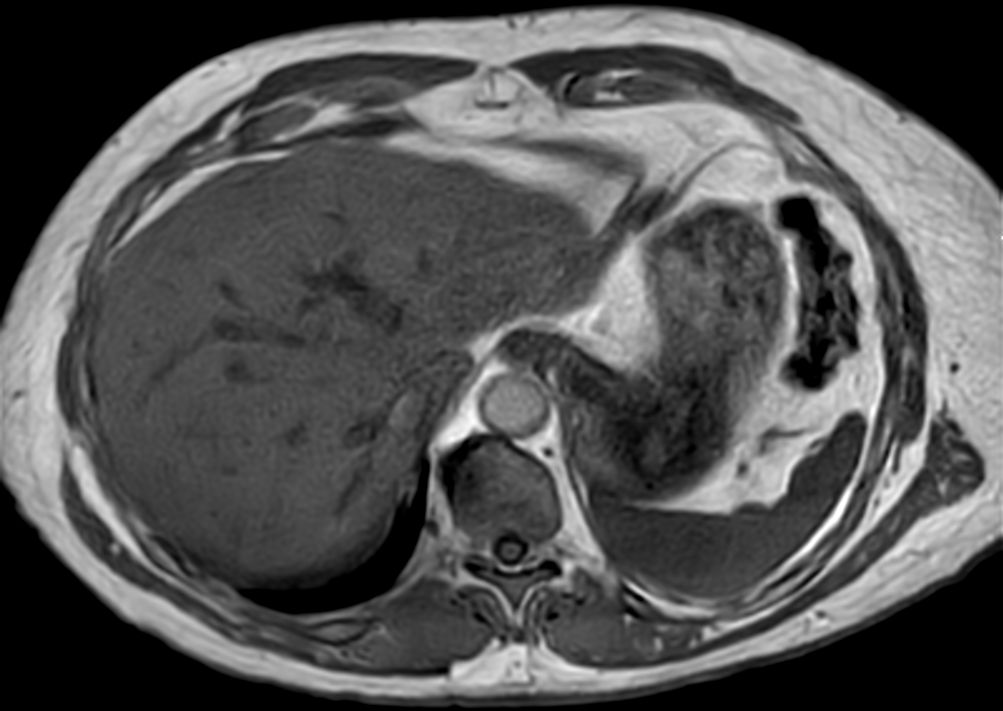

Liver imaging case, leveraging Philips SmartSpeed, our breakthrough new MRI application that delivers image and speed without compromise. Building on our proven technology and leveraging AI* to take fast MRI technology to the next level. Imaging speed is increased while providing greater resolution to deliver outstanding image quality. It covers motion imaging, free-breathing imaging and diffusion-weighted imaging to address the needs of a broad range of patients in various conditions.

Axial T2w TSESmartSpeed Motion-Free